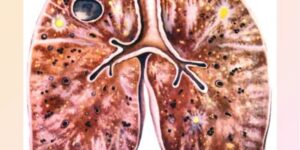

Причины, симптомы и лечение микобактериоза легких

Микобактериоз легких — это воспаление легочной ткани с изменениями структуры и функции органа, вызванное атипичными (нетуберкулезными) микобактериями. Недостаточная информация о возбудителе и отсутствие чувствительных методов диагностики ограничивают возможность точного отслеживания распространенности этого заболевания среди населения. Этот патоген все чаще выявляется у людей, инфицированных ВИЧ. Как выглядит микобактериоз легких клинически? Как это можно обнаружить и лечить? …